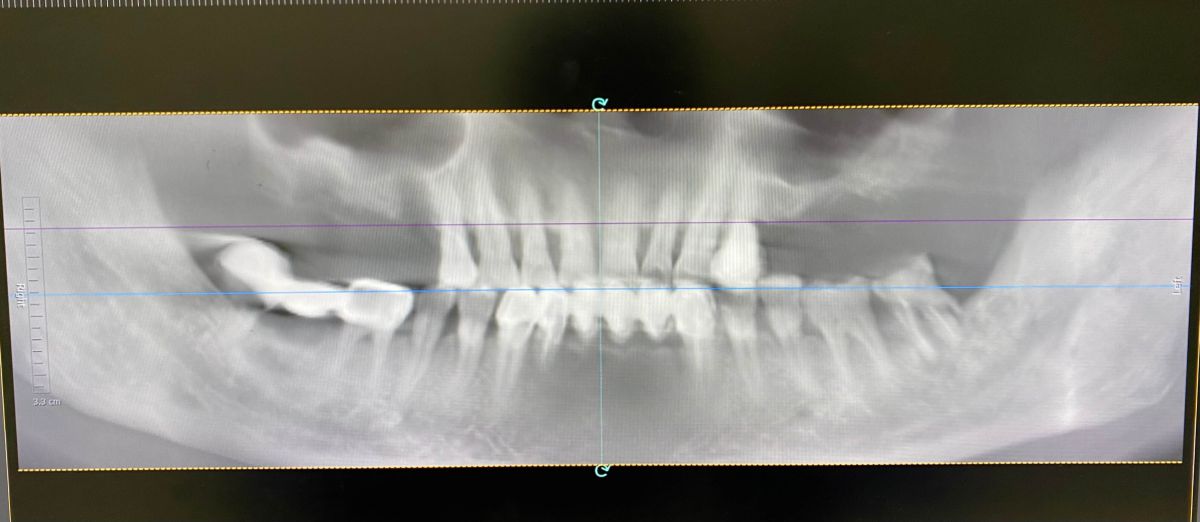

1 Kết quả chuẩn đoán từ phim 3D

Qua chụp CT ConeBeam 3D, bác sĩ ghi nhận chú Hòa mất toàn bộ răng hàm trên hai bên:- Mất răng R15, R16, R17 (hàm phải)

- Mất răng R25, R26, R27 (hàm trái)

- Tiêu xương nghiêm trọng

- Xoang hàm hạ thấp

- Không đủ xương để cấy Implant trực tiếp